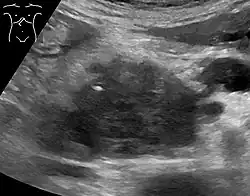

Medical imaging techniques, such as computed tomography (CT scan) and endoscopic ultrasound (EUS) are used both to confirm the diagnosis and to help decide whether the tumor can be surgically removed (its "resectability").[12] On contrast CT scan, pancreatic cancer typically shows a gradually increasing radiocontrast uptake, rather than a fast washout as seen in a normal pancreas or a delayed washout as seen in chronic pancreatitis.[58] Magnetic resonance imaging and positron emission tomography may also be used,[2] and magnetic resonance cholangiopancreatography may be useful in some cases.[34] Abdominal ultrasound is less sensitive and will miss small tumors, but can identify cancers that have spread to the liver and build-up of fluid in the peritoneal cavity (ascites).[12] It may be used for a quick and cheap first examination before other techniques.[59]